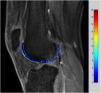

Imágenes de los tiempos de relajación 1Hay estudios que han demostrado que los T1 del cartílago varían con la enfermedad y que se alargan. Estos valores se pueden calcular con secuencias y técnicas adecuadas, principalmente mediante el uso de imágenes consecutivas de la misma región con la variación del ángulo de una secuencia EG. Los mapas paramétricos de los valores de T1 representan una excelente aproximación a las bases moleculares de la degeneración del cartílago (fig. 2).

Los T1 han demostrado que son predictores de la degeneración, incluso antes de que sucedan cambios morfológicos y alteraciones en la señal del cartílago en las imágenes potenciadas en T28. Sus variaciones probablemente se relacionan con las diferentes concentraciones y propiedades de los proteoglicanos con la enfermedad6, ya que se ha demostrado que aumentan lentamente con la edad de los sujetos8. Son, además, imprescindibles para el cálculo subsiguiente de otros parámetros posteriores al proceso que se verán a continuación (como la farmacocinética y la captación tardía).